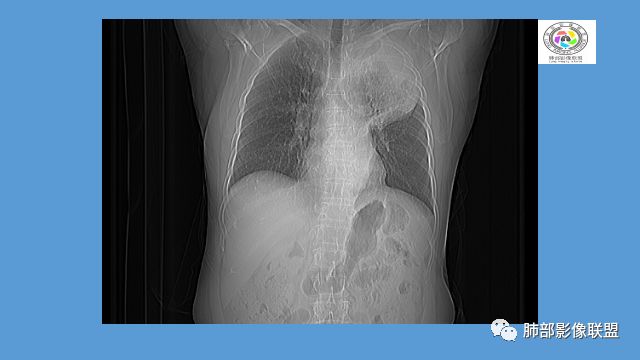

中年女性,反复咳嗽咳痰4月,加重半月,咳嗽,咳黄痰。胸CT:左肺体积缩小,左肺上叶病变,病灶内可见支气管征,病灶边缘可见棘突样改变,病灶周围可见结节状卫星灶,纵隔可见淋巴结肿大,部分淋巴结可见钙化灶。增强CT病灶内可见低密度坏死区,冠状位病灶内支气管可见扩张,病灶整体呈收缩,考虑患者为良性慢性感染性病变,结核?放线?,建议支气管镜检查。

晨读:左肺上叶实变,边缘不整,部分膨隆,其内支气管有狭窄有扩张,周围小叶间隔增厚,左肺下叶背段可见气腔结节,树芽征,边缘模糊,肺门及纵膈淋巴结钙化,考虑结核。鉴别肺炎型肺癌。

1.双肺多发病灶,结节影、树丫影,边缘分布……病灶符合继发性肺结核。

2.左肺上叶大片实变影,密度不均,体积轻度增大,注意轻到中度强化及血管影未见破坏、未见坏死空洞……病灶更符合炎症,而不大支持干酪性结核及肺鳞癌等,后两者的破坏能力是比较强的。

3.支气管阻塞,沿途可见钙化及液性潴留……更符合支气管内膜结核。

综上,双肺继发性肺结核诊断应当成立;左肺上叶大片影,以支气管内膜结核伴阻塞性炎症解释更为合理。